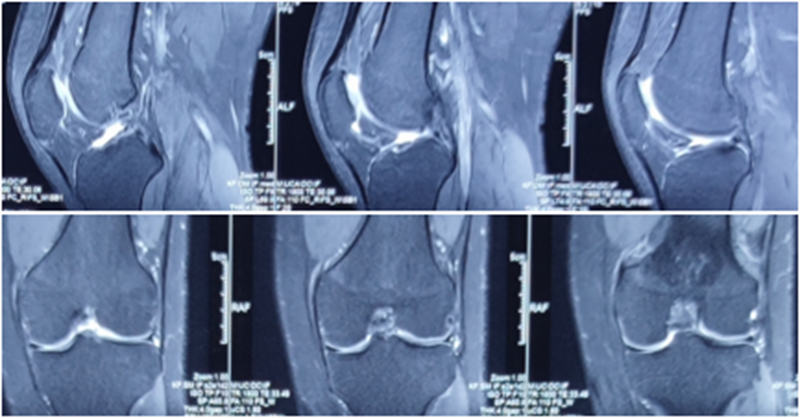

术后MRI

MRI检查评估ACL-R术后——韧带连续性信号好、方向好、愈合快,没有Cyclops综合征。